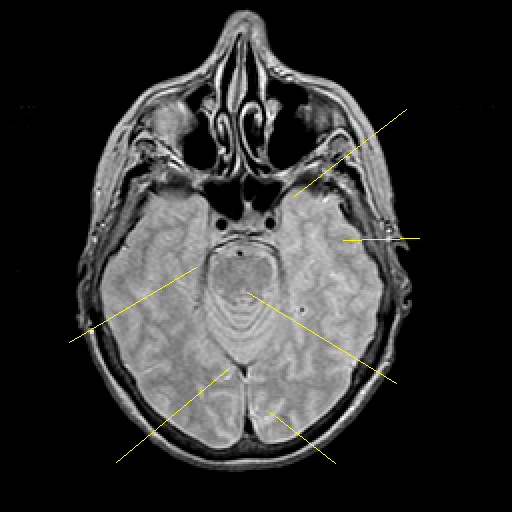

Proton density-weighted structural MR: Slice 18

Slice 18

Pointers

Labeled